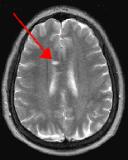

Fig. 2

By turning CSF dark, bright periventricular lesions such as MS plaques become much more conspicuous. Fig. 1 shows a typical T2-weighted axial image of the brain in which CSF in the ventricles appears bright. A lesion on the right is present (red arrow) that is also bright similar to CSF. Fig. 2 is a corresponding FLAIR image showing an obvious bright MS plaque (white arrow) against a background of dark CSF and gray parenchyma with additional more subtle lesions.